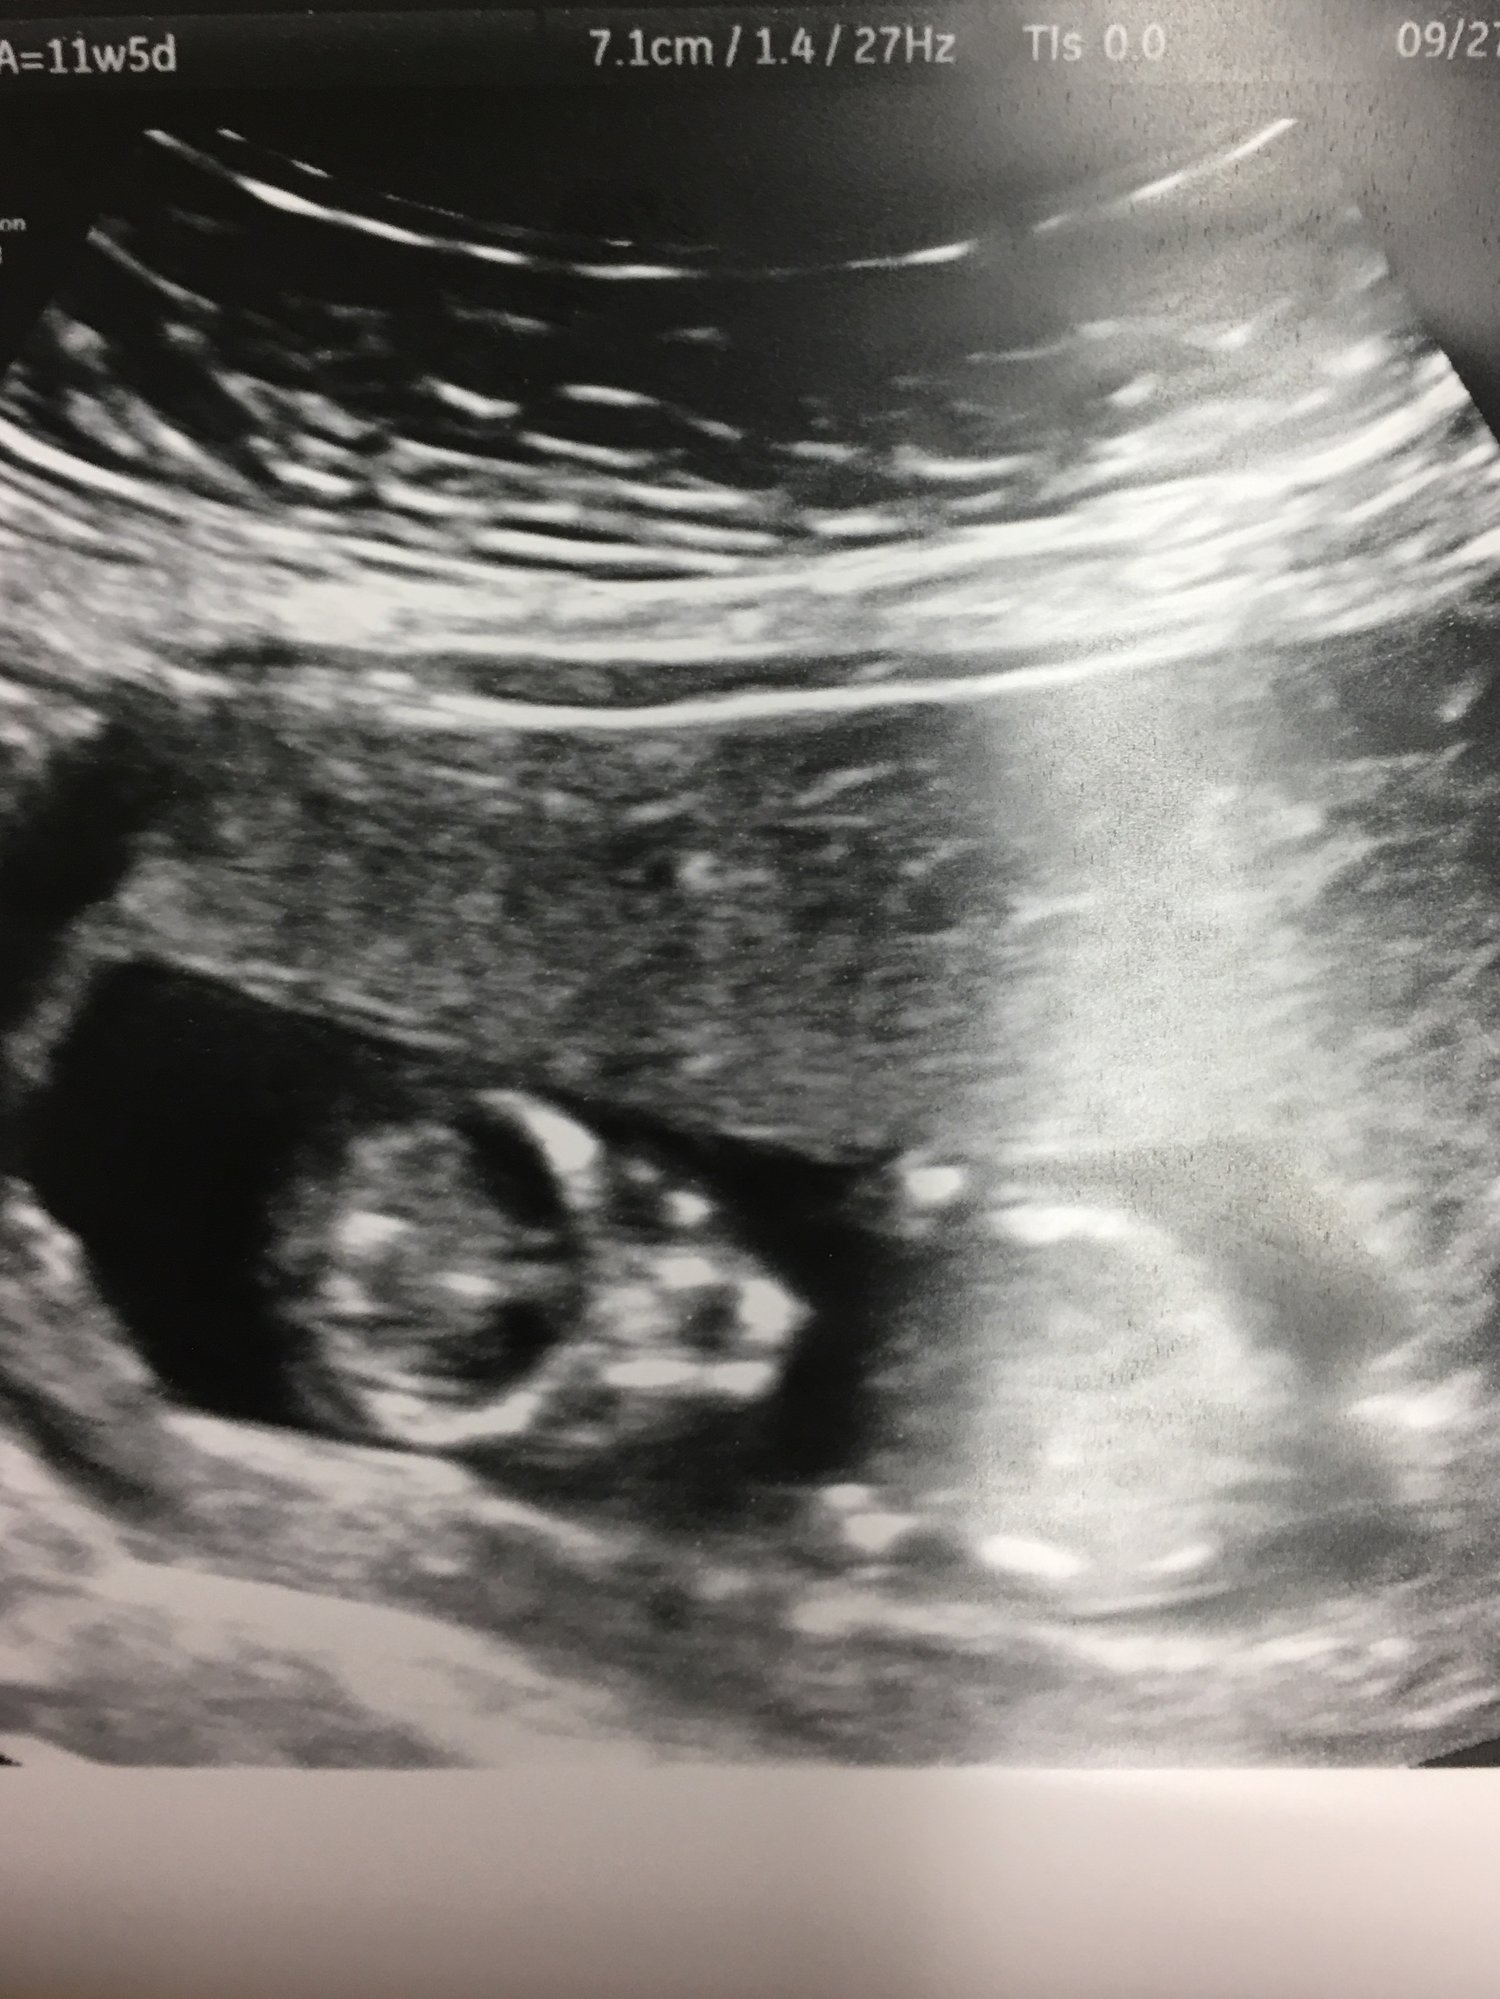

11w2d today! I graduated to my reg OB with low risk genetic results and a 4D u/s! Also found out it's another girl!

@StephieMK oh my goodness! That's the sweetest u/s I've ever seen! Her little arms and legs! So adorable. Congratulations on a baby girl! I have two girls already and can't say I'd be sad about having another one. Haha.

@rbbabe2b Thanks! I'm pretty excited it's another girl! We have a ton of stuff left from DD including lots of unworn clothes with tags so I was hoping to be able to use them.